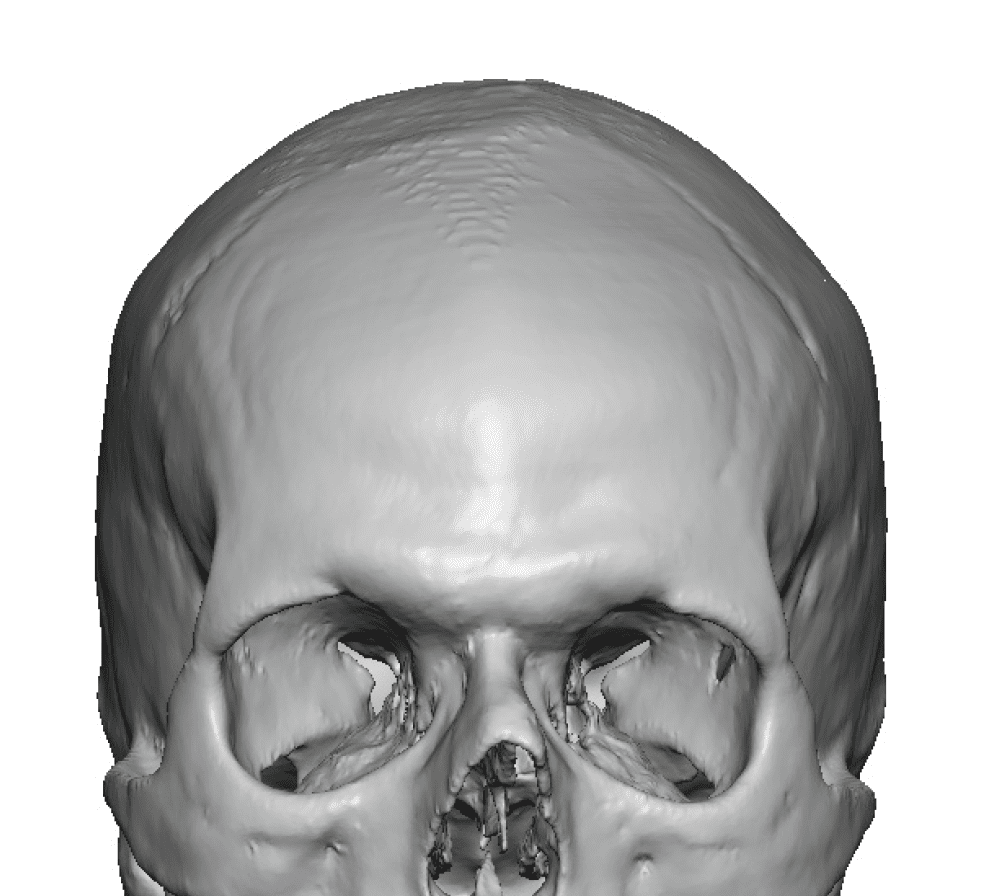

Desire for change of head shape from front view form an inverted V shape to a rounder and wider head shape.

Placement of custom extended forehead-temporal implants through incisions in the crease behind the ear. (he had a prior back of head skull implant which is green in the implant designs and which the head widening implants partially covered it)

Desire for change of head shape from front view form an inverted V shape to a rounder and wider head shape.

Placement of custom extended forehead-temporal implants through incisions in the crease behind the ear. (he had a prior back of head skull implant which is green in the implant designs and which the head widening implants partially covered it)